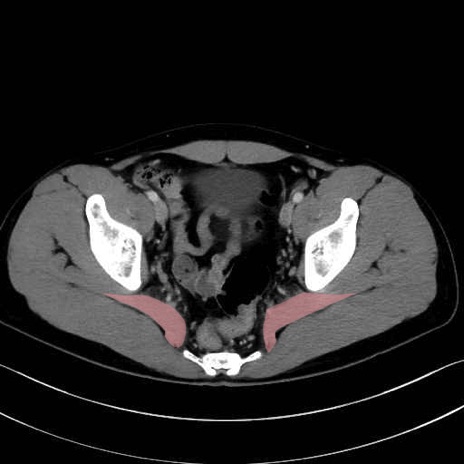

梨状筋 (Piriformis)